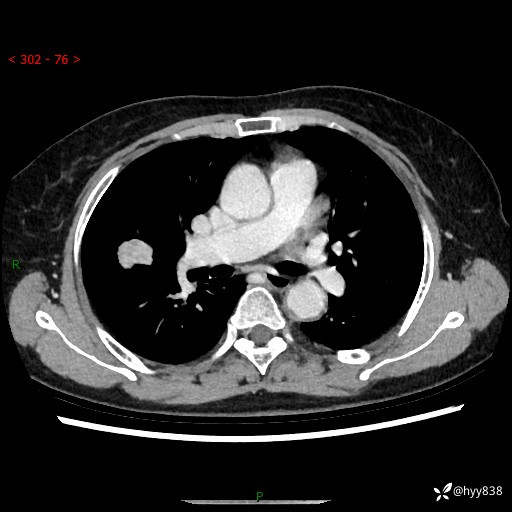

胸部CT平扫+增强